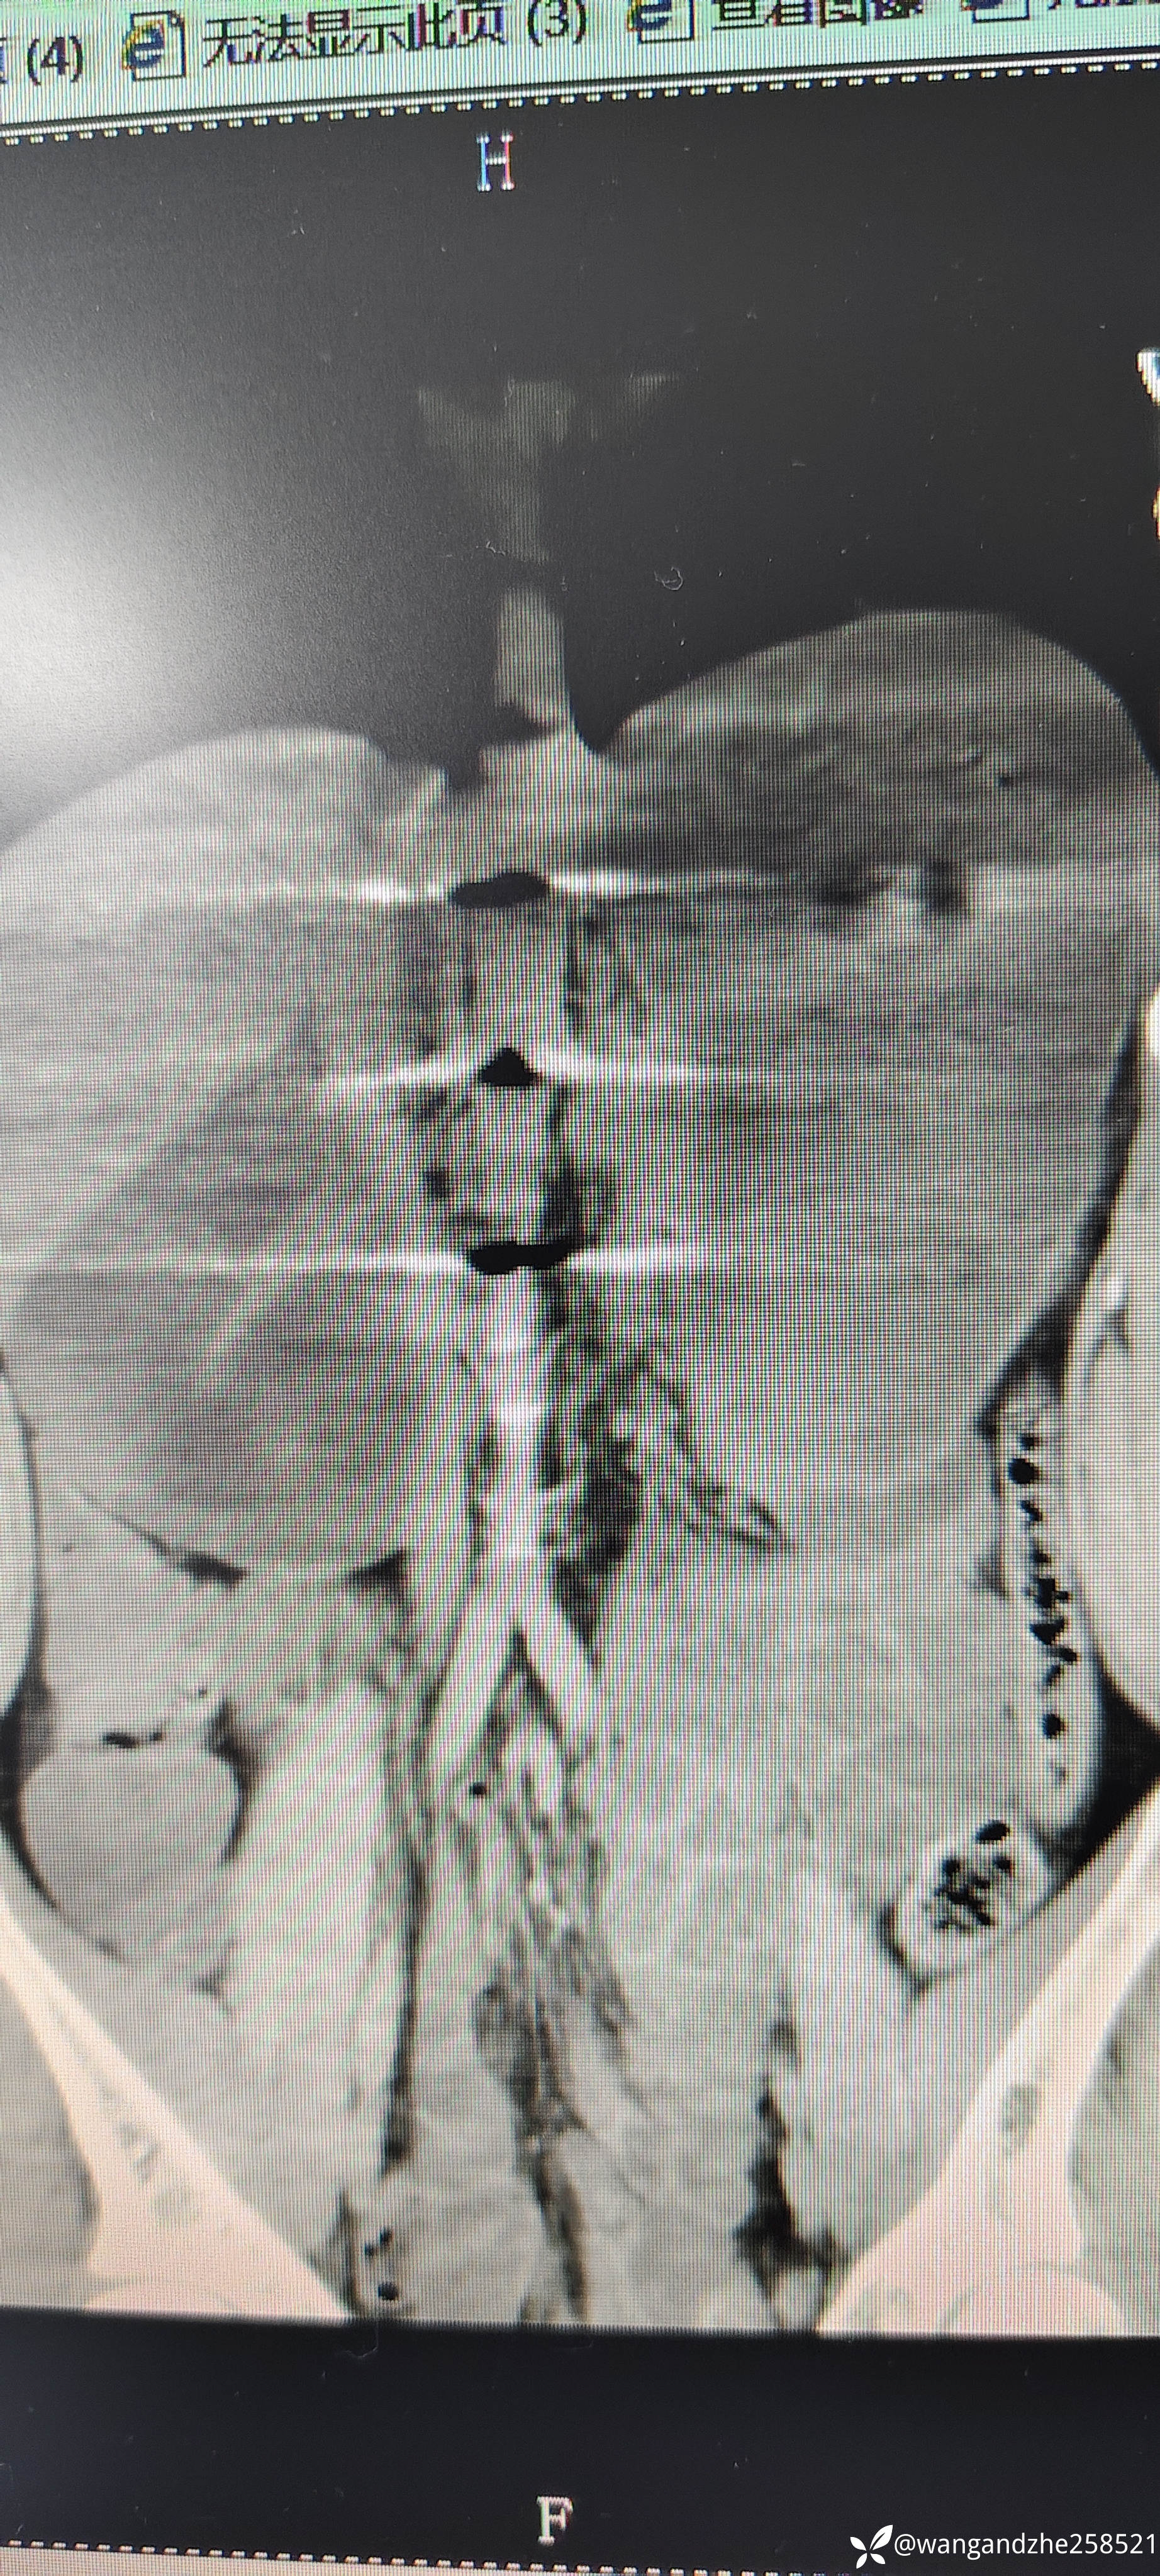

入院后胸部CT未见明显异常,存在疑问,该患者猝死原因是窒息?还是另有其他原因